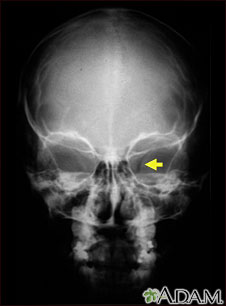

Neurofibromatosis I, enlarged optic foramen

This X-ray shows the skull of a child with neurofibromatosis (NF-1). This child developed visual difficulties and was discovered to have a glioma (nerve tumor) in the optic nerve. The tumor has enlarged the bony opening (optic foramen), through which the optic nerve passes. This can be seen on the right side of picture.